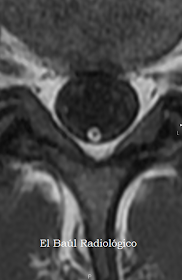

FIGURA 6) Imagen FSE-T1. Lipoma filiforme del Filum. Aparece como un anillo brillante que rodea al Filum.

FIGURA 7) Imagen axial FSE-T1.En esta imagen magnificada, el lipoma se aprecia con más nitidez. Un hallazgo semejante, que aparece en varios cortes axiales, es característico de un lipoma del filum.